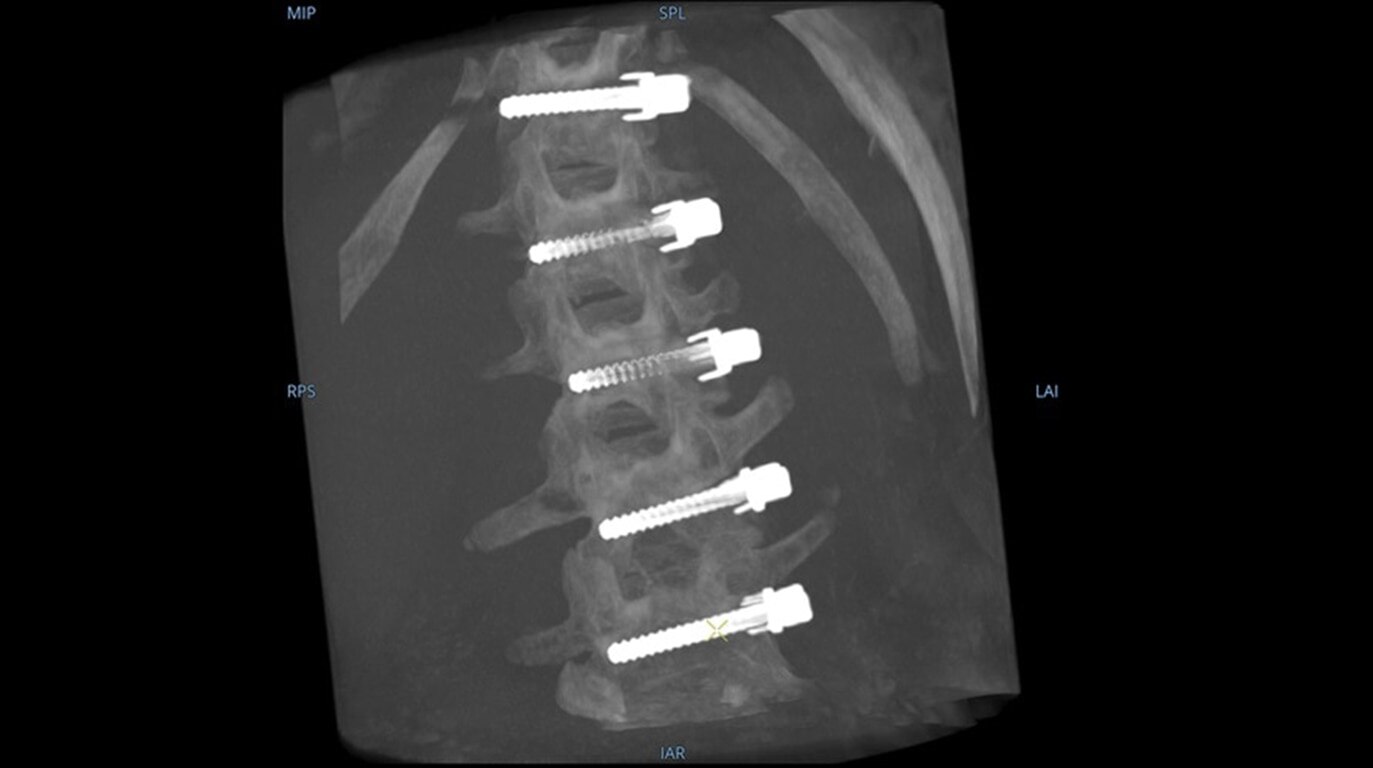

See more levels during a spinal fusion, or more of the pelvis or femur during an orthopedic procedure. With a 19 cm x 19 cm x 19 cm volume, OEC 3D captures a 67% greater volume than other 3D C-arms*.

Enhance intraoperative decision-making with visualization capabilities of Augmented Fluoroscopy in the OEC 3D Volume Viewer. Analyze five perspectives with 3D imaging tools including Multi-Oblique Mode, scrolling 512 slices, zoom, and more.